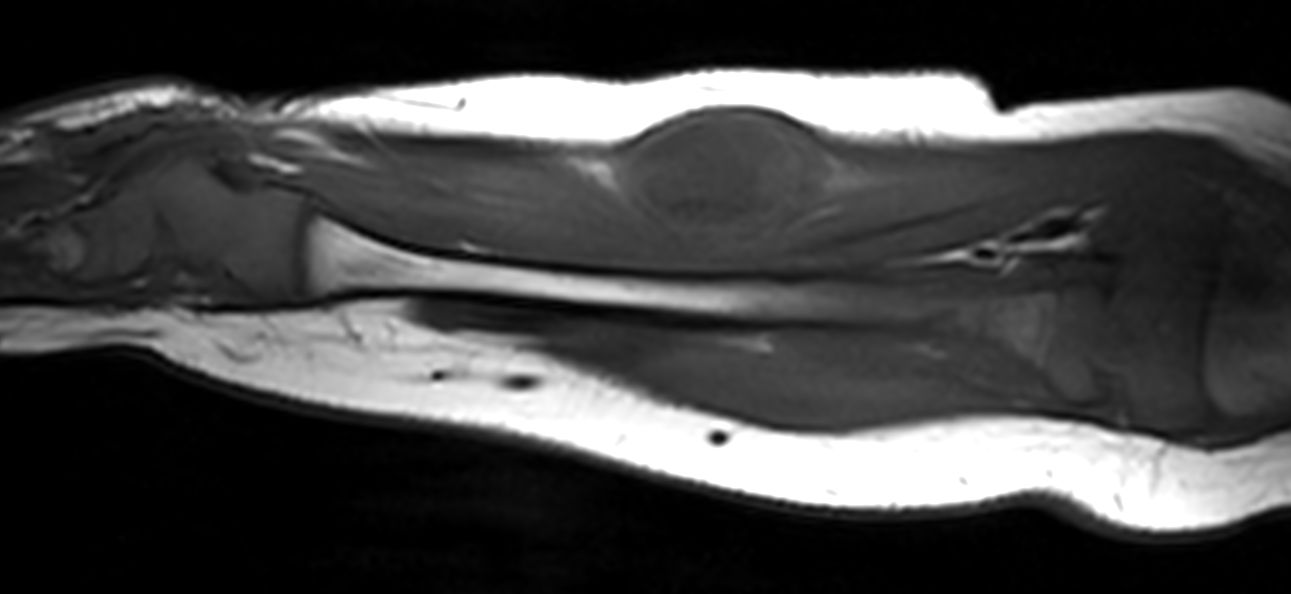

Pediatric patient with a lesion in the forearm. mDIXON XD provides uniform fat-free imaging and allows for multiple image types in one single scan. Integration of Compressed SENSE acceleration technique enables speeding up of the entire exam.

Coronal T2w mDIXON XD (In Phase)Compressed SENSE